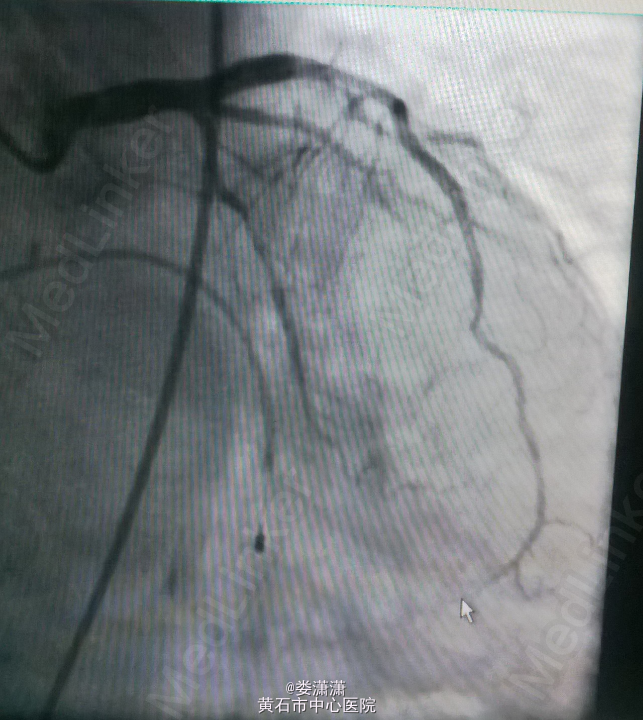

诊断:1.急性下壁心肌梗死(STEMI),心源性休克,心功能IV级(killip分级);2.高血压病2级(很高危);3.2型糖尿病;4.陈旧性脑梗塞;5.高尿酸血症。 处理——收入CCU后立即转去导管室行急诊冠脉造影术,术中见右冠中段以远全部闭塞,未见侧枝循环,前降支近中段见节段性狭窄70-80%,术中经6F Thrombuster血栓抽吸导管反复多次抽吸右冠,抽出数条红色血栓,并于右冠中段病变处植入Firebird 4.0*23mm药物支架,缝合鞘管时患者心电监护提示加速性实行逸博心律(110次/分左右),5min后突发室速、室颤,立即予床边电极除颤后转位室性逸博心律(105次/分)。返回病房后夜间患者多次出现室颤,予点击除颤、胺碘酮静滴等治疗后好转。术后24h内患者出现少尿,予静脉补液(5000ml/天左右)、利尿等,患者尿量基本维持在2000ml/天。术后辅查心电图见下壁导联ST段明显回落。余予抗血小板聚集、稳定斑块等治疗。